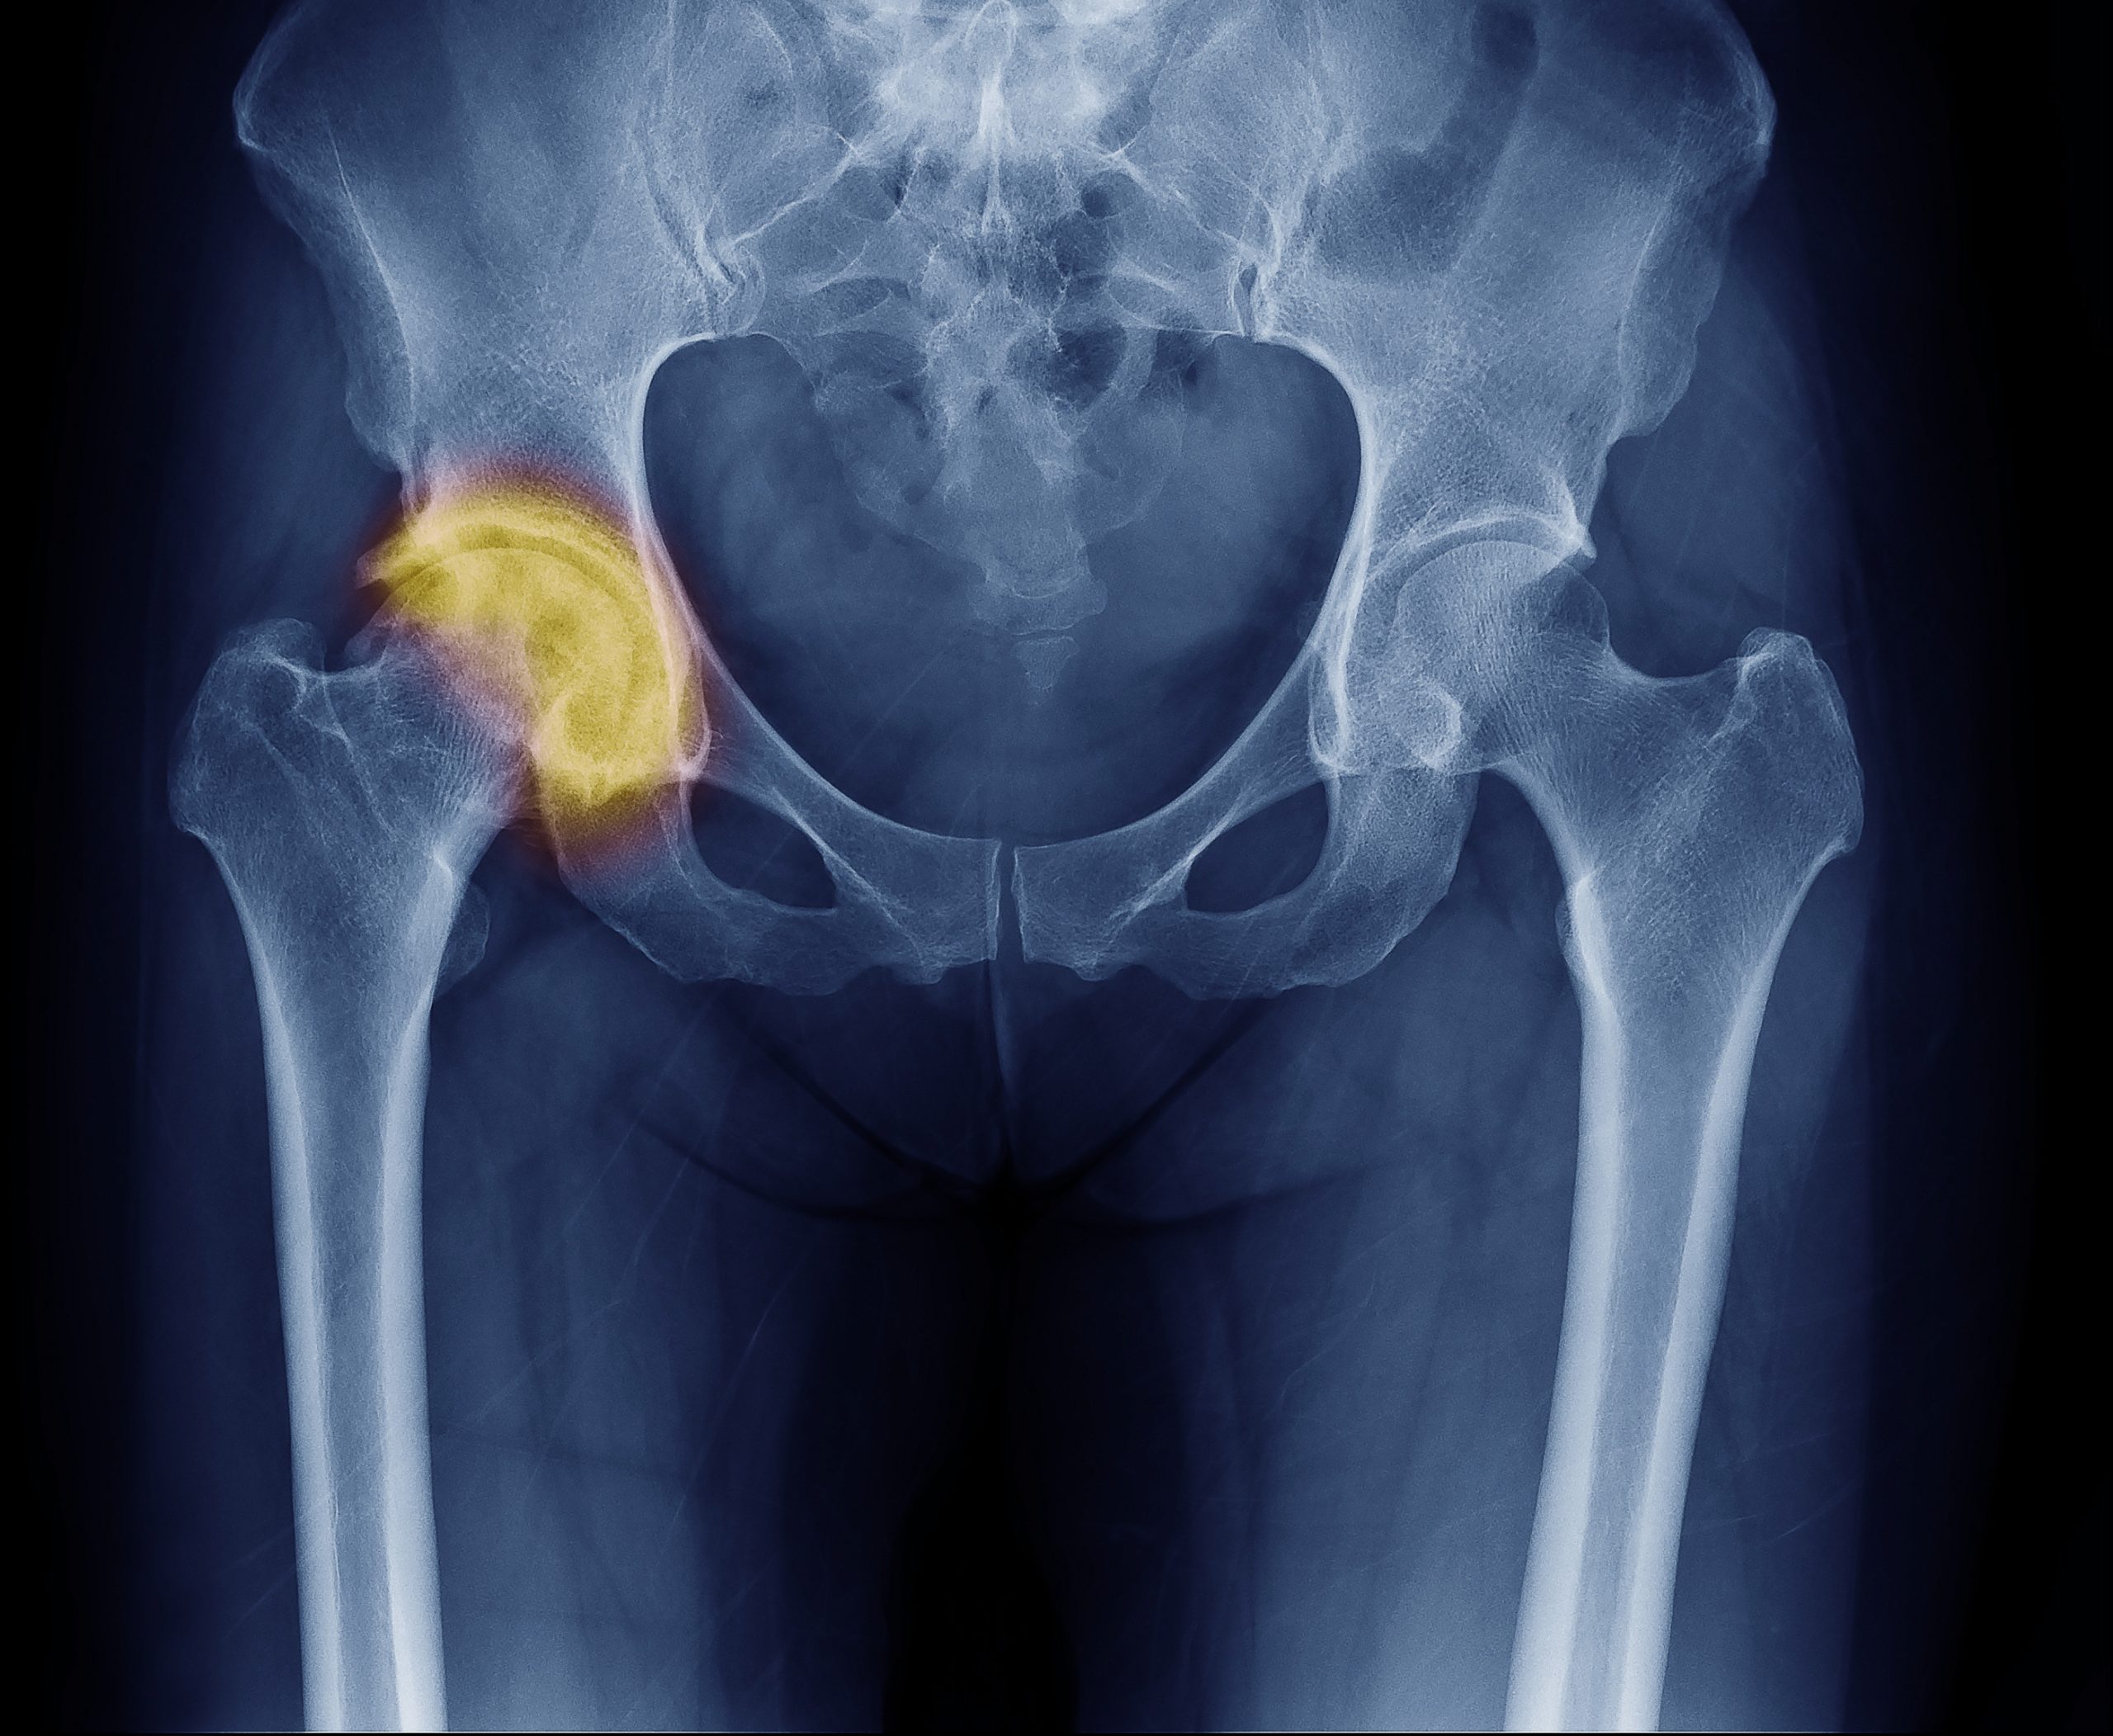

Złamanie osteoporotyczne biodra

W osteoporozie najczęściej dochodzi do złamania bliższego końca kości udowej. Wyróżnia się m.in. złamanie wewnątrztorebkowe i pozatorebkowe, które dodatkowo mogą być podkrętarzowe i przezkrętarzowe. Do złamania biodra zazwyczaj dochodzi podczas upadku z wysokości, która nie musi być duża. Jak się szacuje, tylko 10 proc. wszystkich złamań końca bliższego kości udowej, czyli właśnie biodra, ma przyczynę inną niż upadek z wysokości ciała.